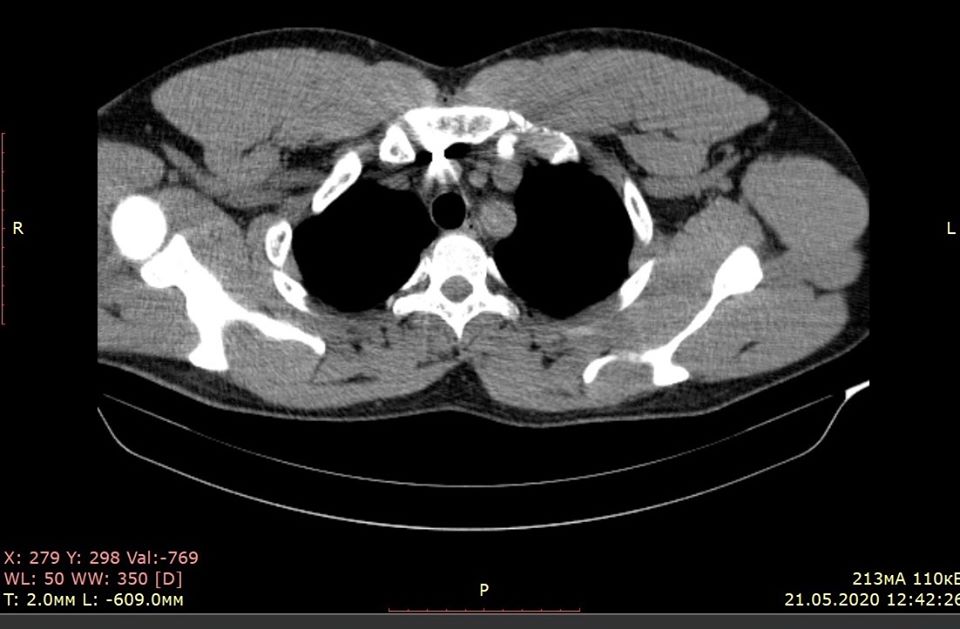

"На півдорозі до безодні. Офіцери. Сергію 33. Його тіло "нафаршироване" осколками. Вибух протипіхотної міни (чорна вдова) забрав друга-командира (полковника поліції Сергія Губанова). Великий шрам на грудях після операції - вічне нагадування про війну. Осколок лежав на аорті поблизу серця. Кращі торакальні хірурги Гліб Шкарупа та Андрій Снісарь провели блискучу операцію в лікарні Мечникова", - зазначив він.